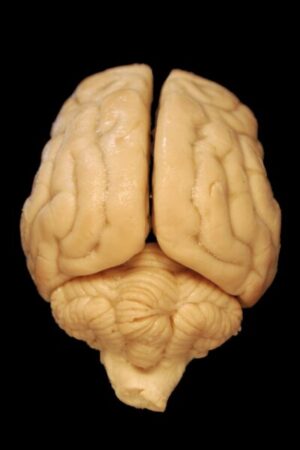

Consequences of Excess CS fluid in and around the Brain

From my training and research, I know how important CS fluid is for many brain and spinal cord functions – protection from injury, providing nutrients to brain and other nerve cells, removing wastes, transporting hormones and ions, and many other tasks. The entire Central Nervous System (CNS) depends upon free flow of the CS fluid within the Cranial-Sacral system.

One of the key characteristics of this fluid is that it is manufactured from oxygenated blood within the brain, while also being drained out to the circulatory system carrying waste products from the brain and spinal cord. This process of adding more fluid and draining some out occurs in cycles day and night for your entire life.

If the CS fluid is continually added around the brain tissue without a similar amount of draining, pressure builds up on the brain. Too much pressure can result in pathological symptoms such as those found in NPH and other forms of hydrocephalus.